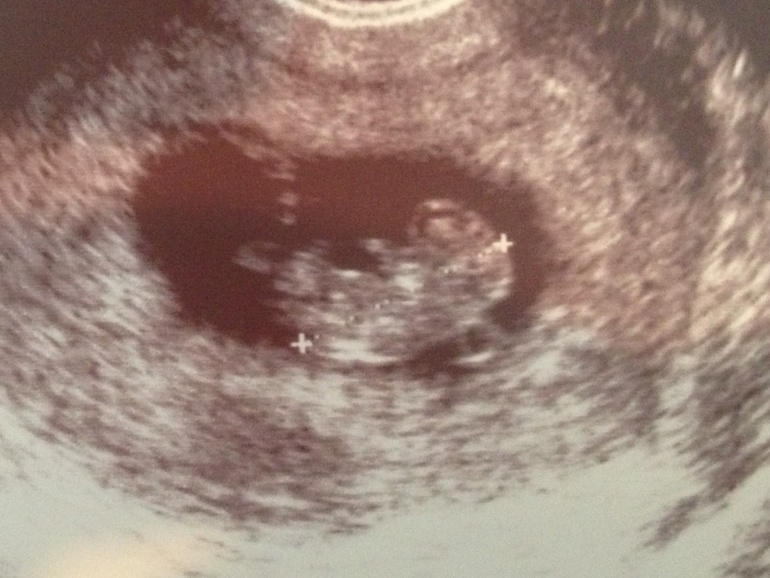

УЗИ, КТГ, доплерСходила сегодня на узи малыш четко соответствует сроку 9 недель и 6 дней, ктр 26мм, сердечко 169 ударов. Прикрепился по задней стенке, а это значит шевелюхи рано почувствую ураааааа.Такой махонький, а уже ручки и ножки хорошо видны и он ими дрыгал, класссс!!!! Теперь жду скрининг 22 ноября ухххххх. А вот и мы, красивые и здоровенькие ттттттттттттттттт